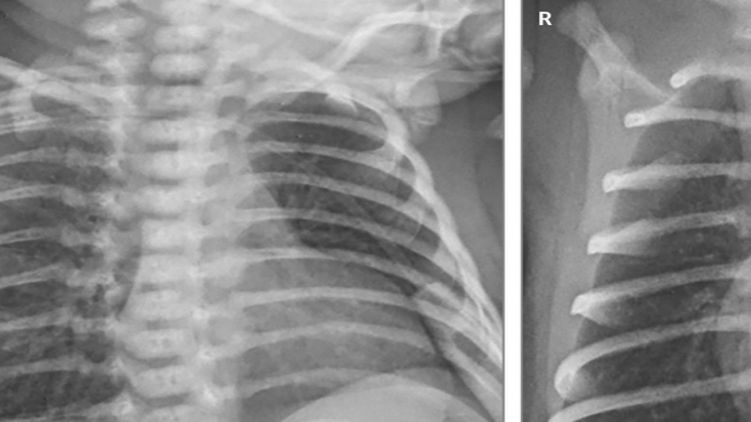

Кроме пневмонии, у двоих маленьких пациентов проявилась лихорадка, а у недоношенного ребенка, который родился после 31 недели беременности, было подозрение на сепсис, который лечили антибиотиками. В отделении интенсивной терапии они провели 2, 4 и 11 дней (больше всего - недоношенный ребенок, ему также понадобилась искусственная вентиляция легких). Все остались живы.